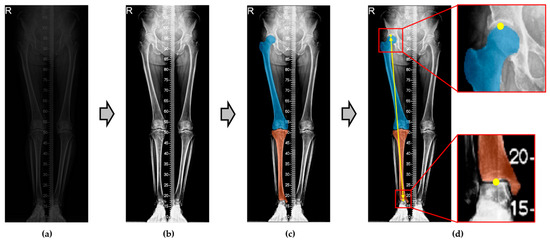

- (a)

- Segment Femur and Tibia: In this step, the femur and tibia are identified from the X-ray data provided by CSU hospital. Details are described in Section 2.3.1.

- (b)

- Key point extraction: To measure the lower-limb length, key points must be identified on the femur and tibia. In this process, key points are accurately extracted from the segmented femur and tibia. Details are provided in Section 2.3.2.

- (c)

- Lower-Limb Length Measurement: The final step involves calculating the Euclidean distance between the extracted key points to obtain the final result. More information can be found in Section 2.3.3.

- Semantic segmentation (for detail, see Section 2.3.1): first, the preprocessed lower-limb X-ray images are semantically segmented into two classes, the femur and tibia.

- Key point extraction (for detail, see Section 2.3.2): from the semantically segmented regions, we extract two key points necessary for the calculations.

- Lower-limb length calculation (for detail, see Section 2.3.3): to determine the lower-limb length on each side, we calculate the Euclidean distance between the key points on the left and right sides.